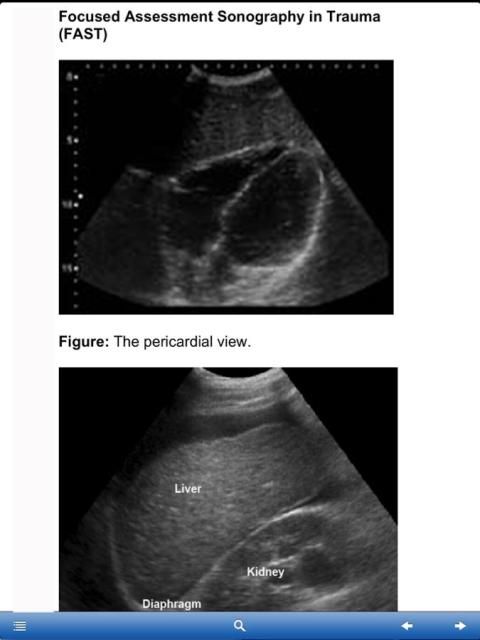

Fokus Penilaian Sonografi Trauma